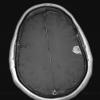

NEOPLASMS (MENINGIOMA)

Lymphoplasmacyte-rich